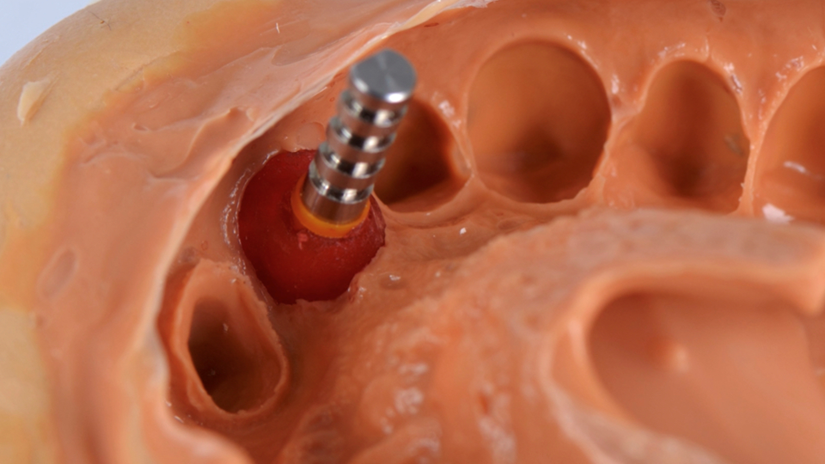

A paciente apresentava queixas estéticas e funcionais. Após avaliação clínica e radiográfica, optou-se pela substituição do pilar reto por um pilar Ideale angulado de 17 graus e 3,3 mm de diâmetro. Esse componente mais estreito e angulado permitiu corrigir o eixo emergente da futura coroa, viabilizando o planejamento de uma prótese parafusada na região estética.

O caso foi conduzido com planejamento cuidadoso, moldagens analógicas e provas clínicas. A reabilitação foi finalizada com a instalação de uma coroa metalocerâmica parafusada, garantindo estética, funcionalidade e reversibilidade do conjunto protético.

Esse protocolo evidencia como a seleção correta do pilar protético, respeitando angulação e diâmetro adequados, pode contornar limitações anatômicas e transformar um caso potencialmente desfavorável em um resultado previsível e satisfatório.